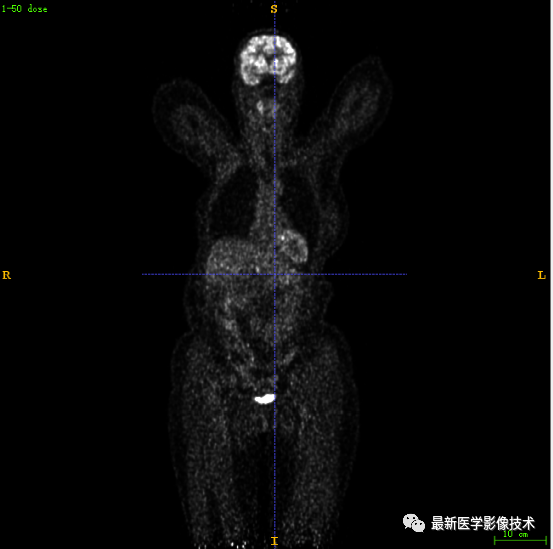

7.4、低剂量20重建结果

第一张是低剂量20的PET图像,第二张是full剂量PET图像,第三张是网络重建的PET图像。